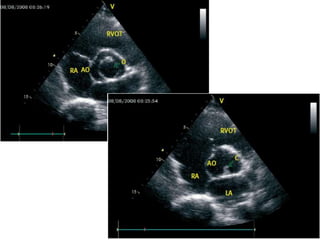

2D Echo-Short axis view

Diastole Systole

Y or inverted Mercedes-Benz sign

2D Echo-Short axisview Diastole Systole Y or inverted Mercedes-Benz sign